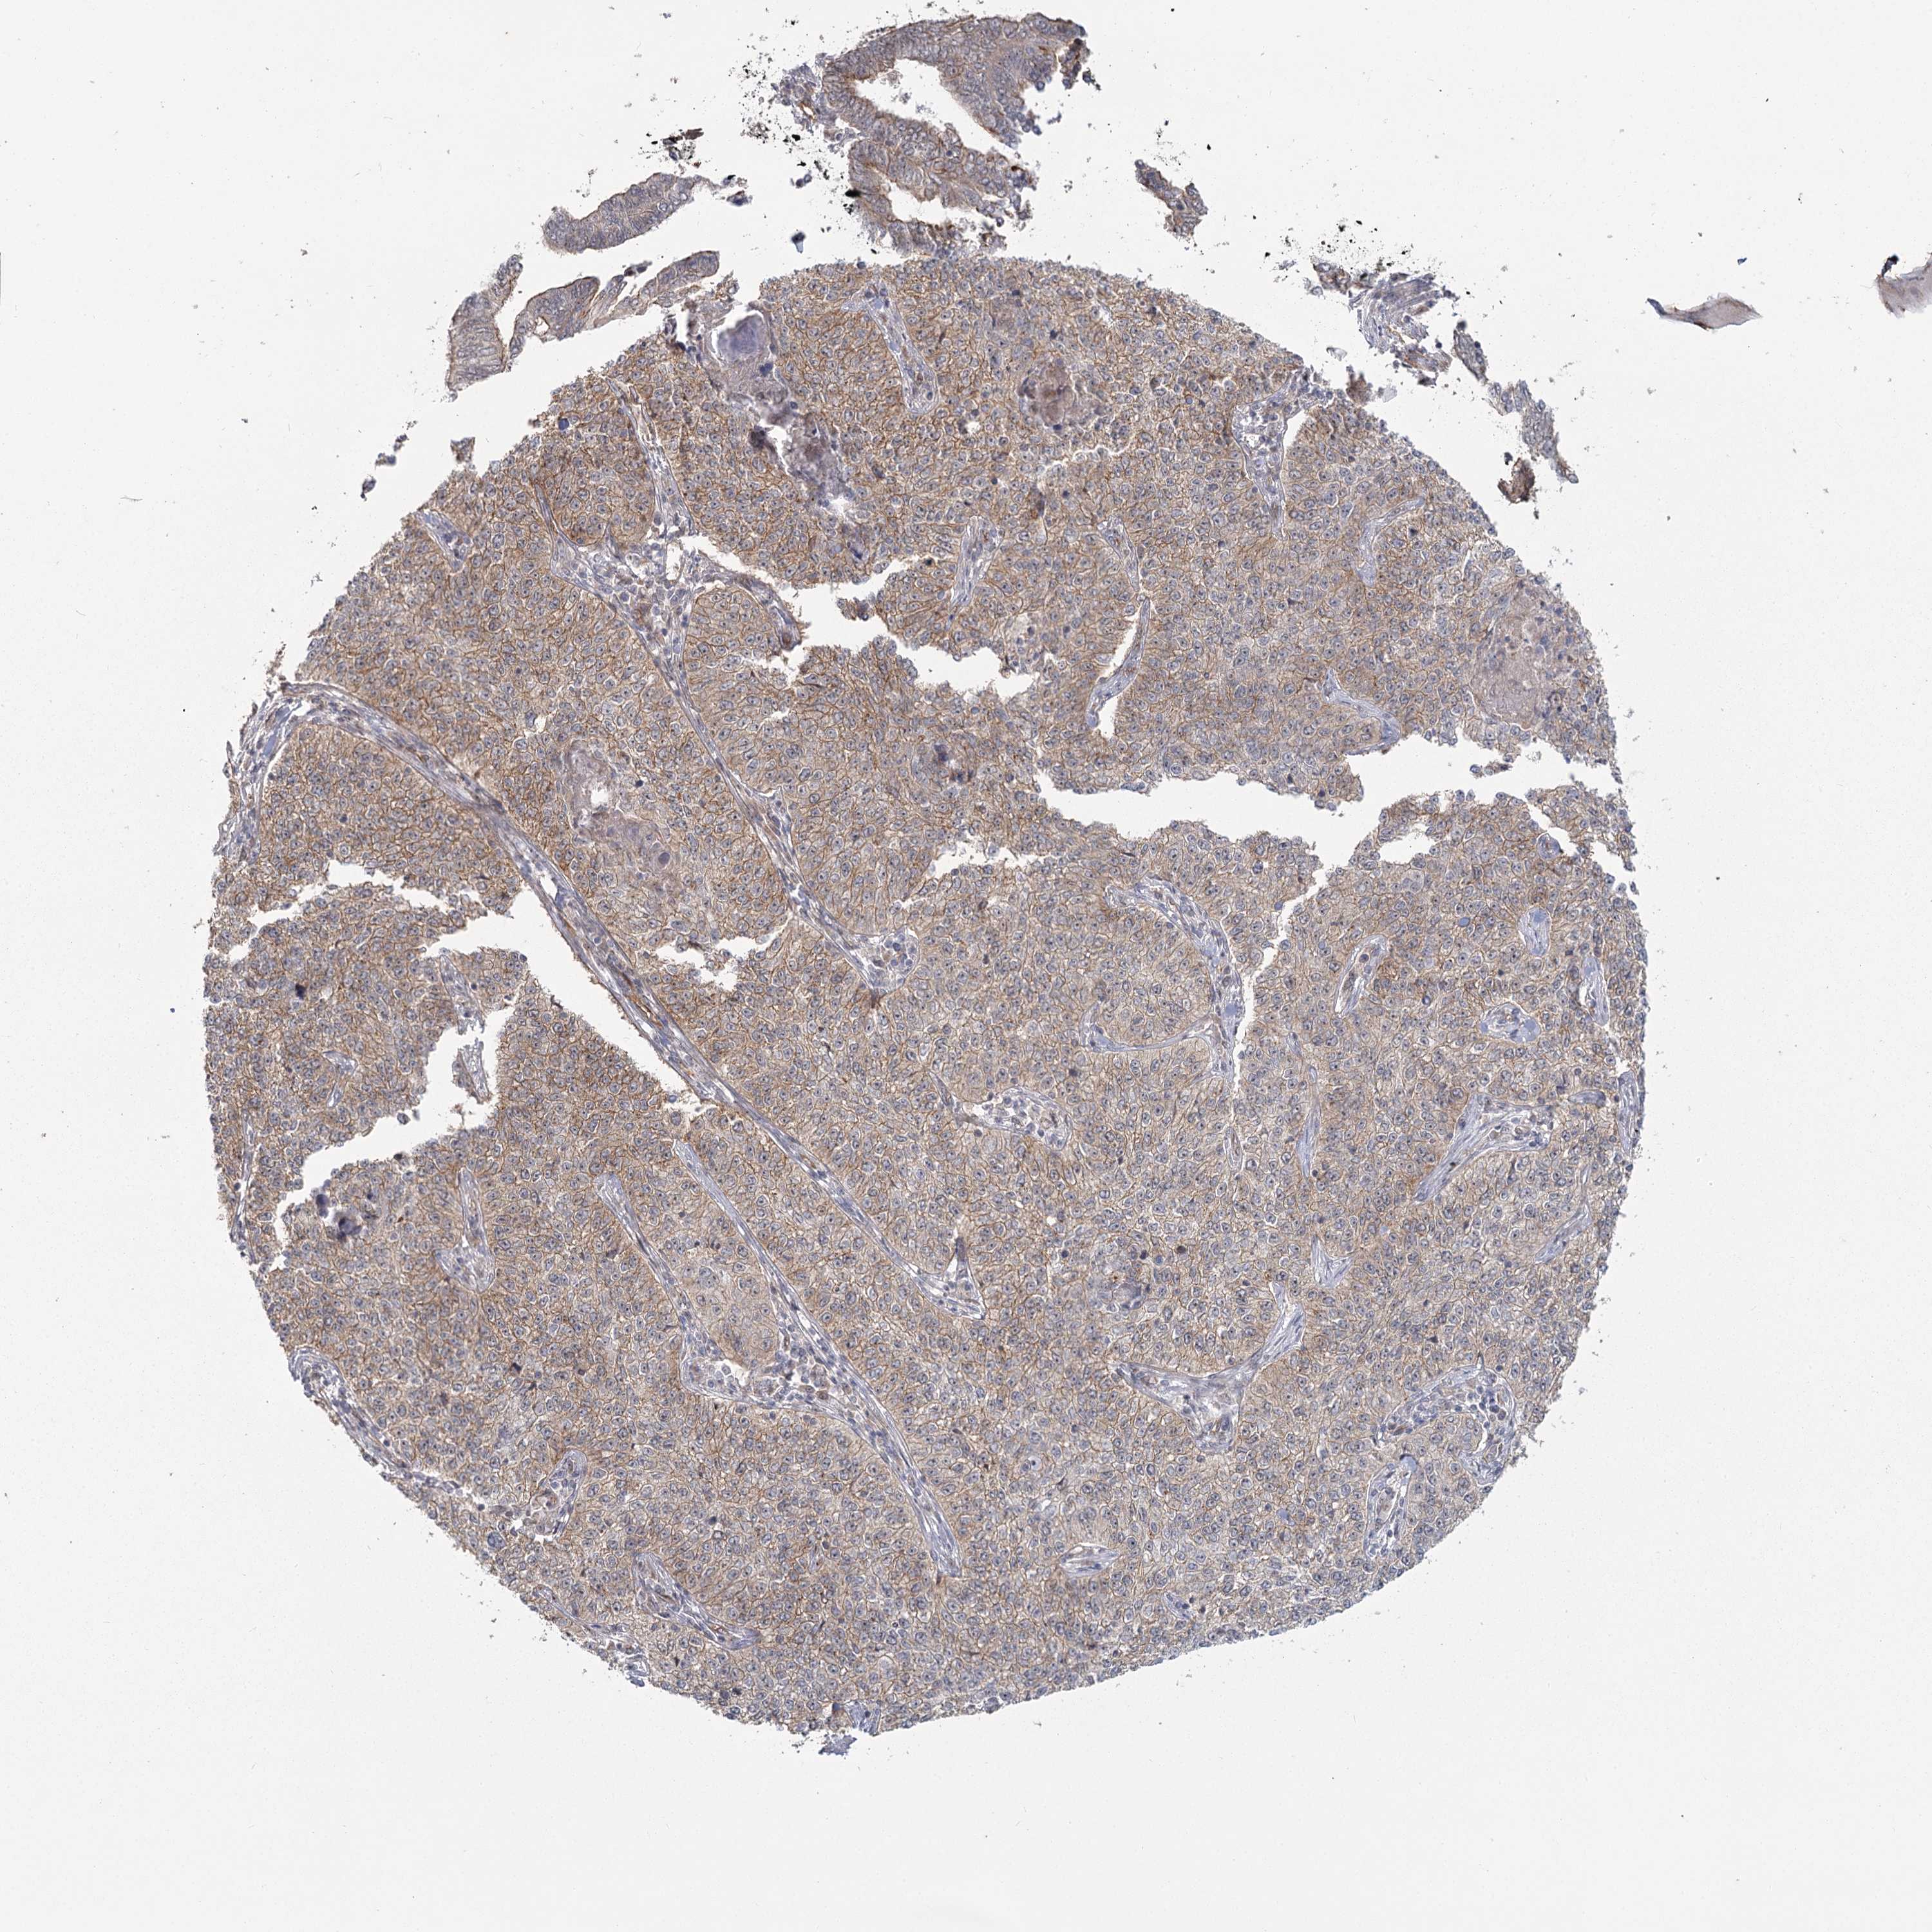

CERVICAL CANCER - Protein expressioni

A mouse-over function shows sample information and annotation data. Click on an image to view it in a full screen mode. Samples can be filtered based on level of antibody staining by selecting one or several of the following categories: high, medium, low and not detected. The assay and annotation is described here.

Note that samples used for immunohistochemistry by the Human Protein Atlas do not correspond to samples in the TCGA dataset.

Antibody stainingi

Antibody staining in the annotated cell types in the current human tissue is reported as not detected, low, medium, or high, based on conventional immunohistochemistry profiling in selected tissues. This score is based on the combination of the staining intensity and fraction of stained cells.

Each image is clickable and will lead to virtual microscopy that enables deeper exploration of all samples and also displays staining intensity scores, fraction scores and subcellular localization as well as patient and tissue information for each sample.

Antibody HPA036194

Staining

High

Medium

Low

Not detected

Intensity

Strong

Moderate

Weak

Negative

Quantity

>75%

75%-25%

<25%

None

Location

Nuclear

Cytoplasmic/membranous

Cytoplasmic/membranous,nuclear

Squamous cell carcinoma, NOS

Adenocarcinoma, NOS